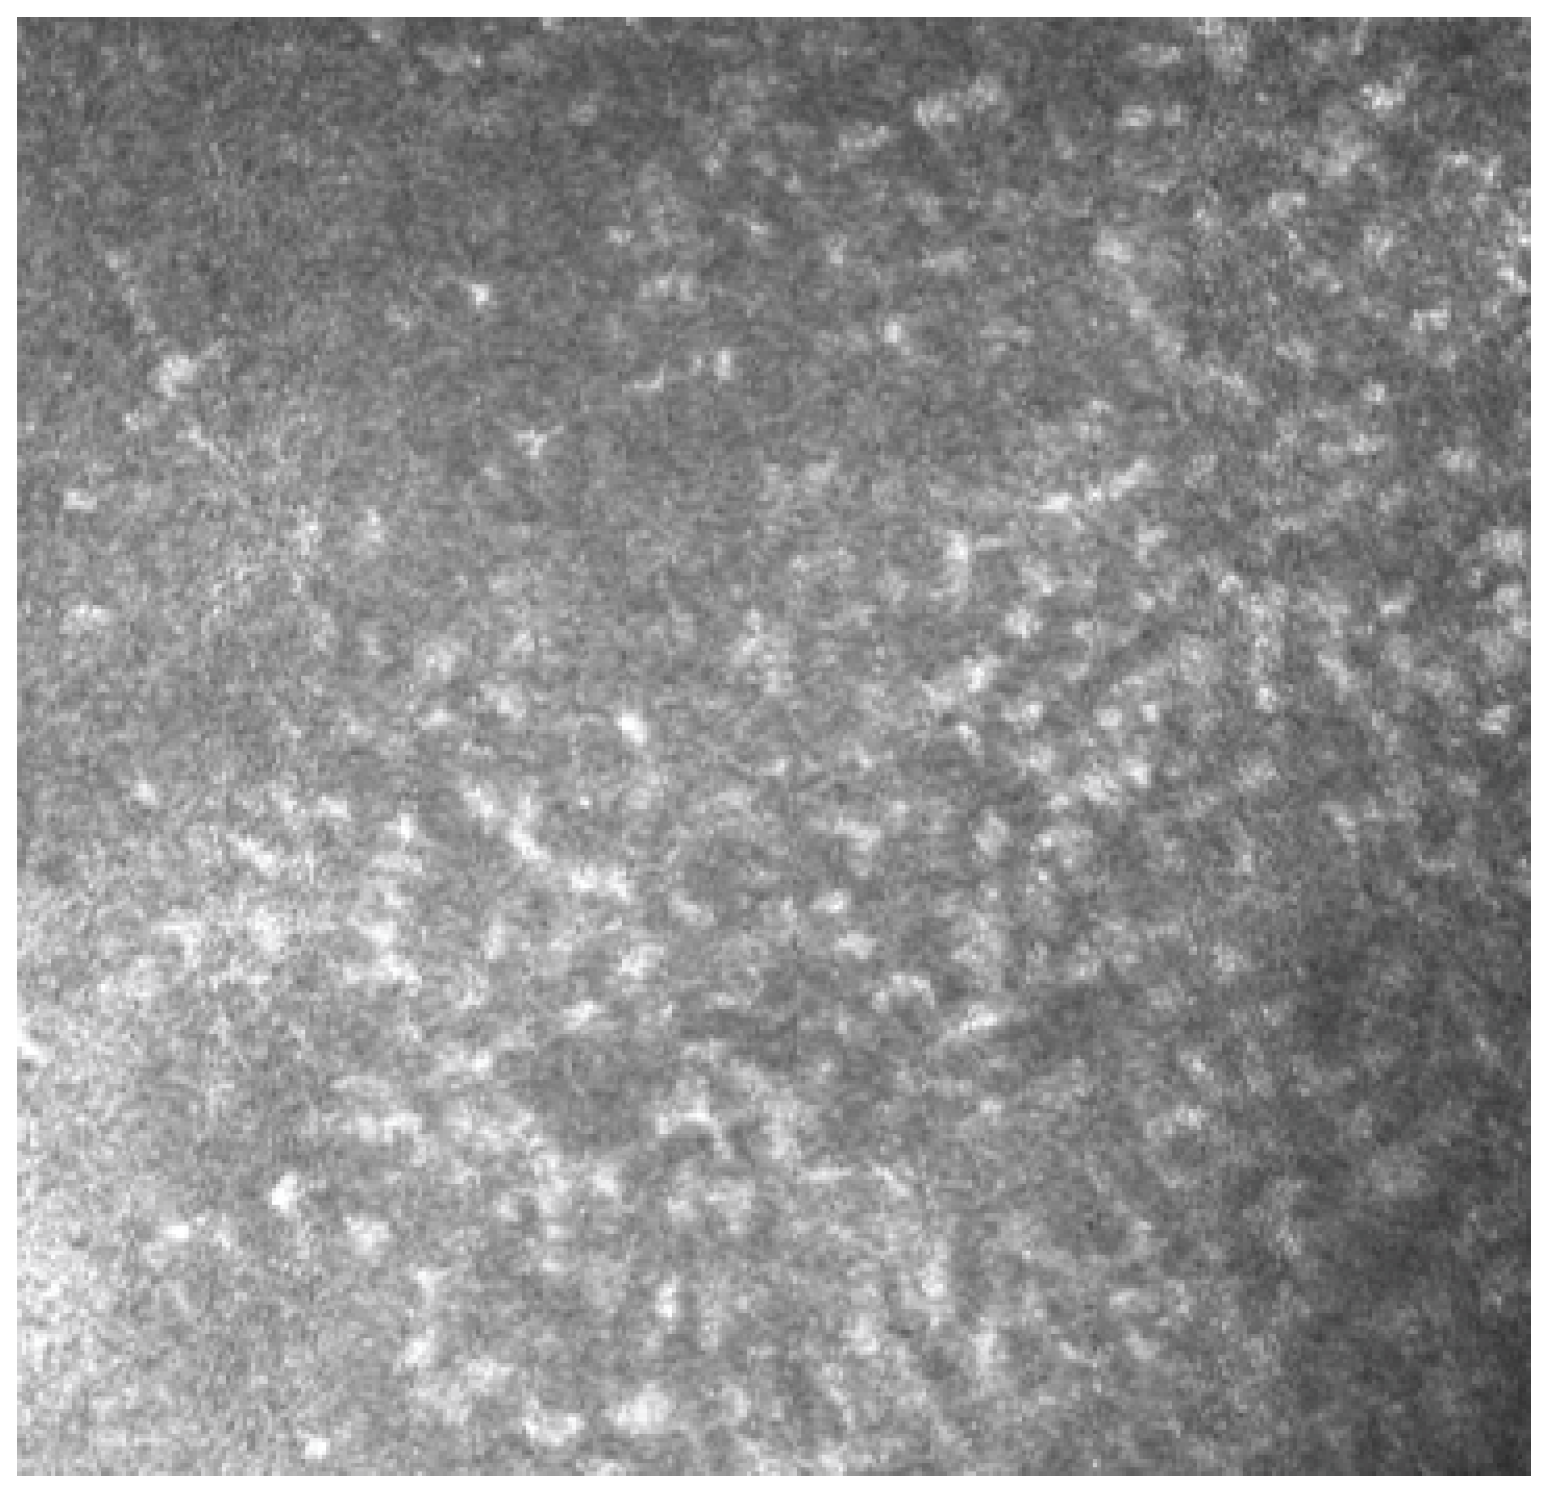

In Group 2, we observed that both eyelids showed mild-to-moderate distorted anatomy at Meibography. At the confocal examination, we observed a decrease in the goblet cell population in the conjunctival epithelium in this group (5.2 cells/mm); in some cases, goblet cells totally disappeared (Figure 5). In tarsal conjunctiva, inflammatory cells were present, and more concentrated around the adenoid lumina of the meibomian glands. We observed several cell infiltrates, composed of a mix of round cells and cells with multilobate nuclei compatible with neutrophils, which were probably a sign of an inflammatory process involving the conjunctiva (Figure 6).

Meibomian glands showed up as hyperreflective, edematous, and with a dilated acinar structure with a blurred lumen contour, that can be referred to as a meibomitis sign.

In vivo confocal microscopy provides non-invasive high-resolution images of ocular surface tissues, bypassing the need for biopsy and/or impression cytology. Our in vivo images of bulbar and tarsal conjunctiva, acquired by confocal microscopy, confirmed the reduction in intraepithelial goblet cells as reported in the literature in patients treated with Dupilumab (Figure 5) [7]. Goblet cells are round cells, that occur mainly individually or in clusters, and normally account for 10% of the conjunctival epithelial cells [17]. We found a mean value of 5.2 cells/mm. In addition, the in vivo images show inflammatory cells in the tarsal conjunctiva and around the adenoid lumina. We assumed that the inflammation could be the cause behind the dropout of glands.

Figure 6. In vivo images of bulbar conjunctiva of a treated patient: several cell infiltrates are present, probably a sign of an inflammatory process involving the conjunctiva.